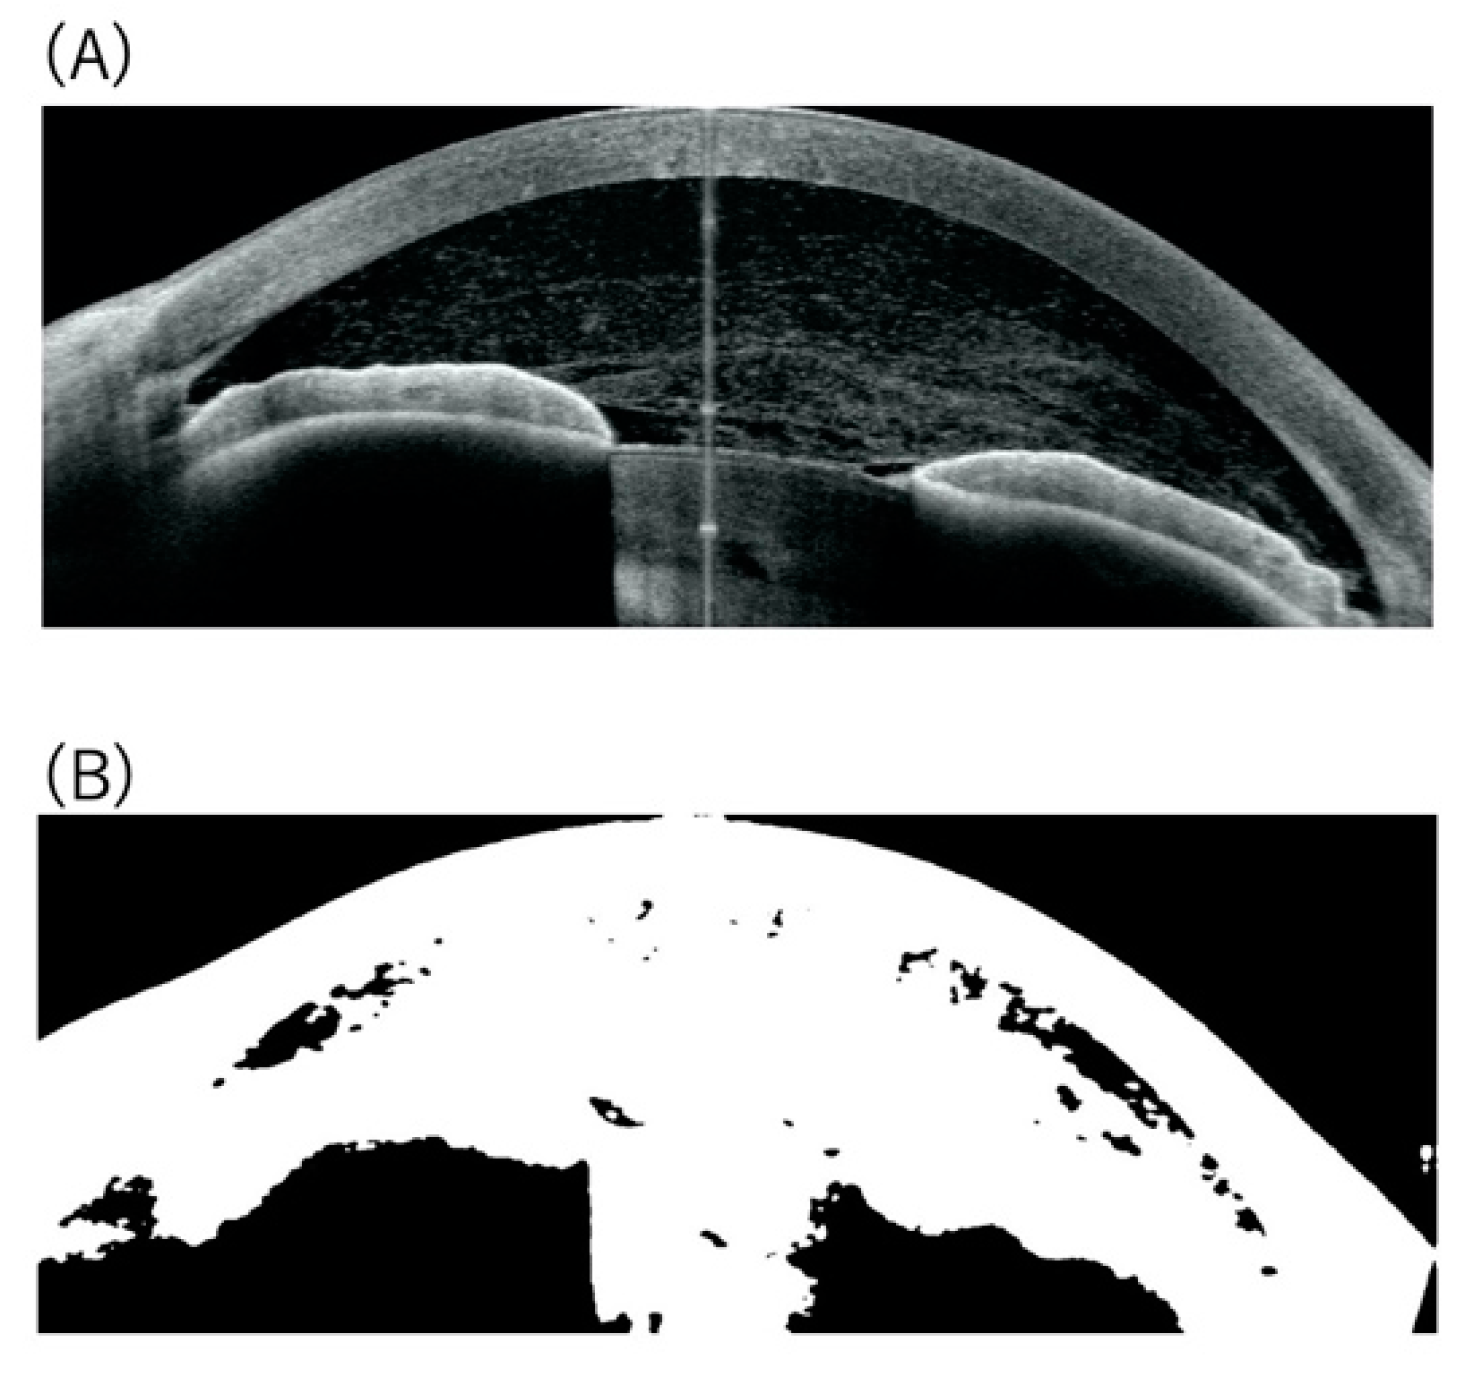

2.3. Image Analysis